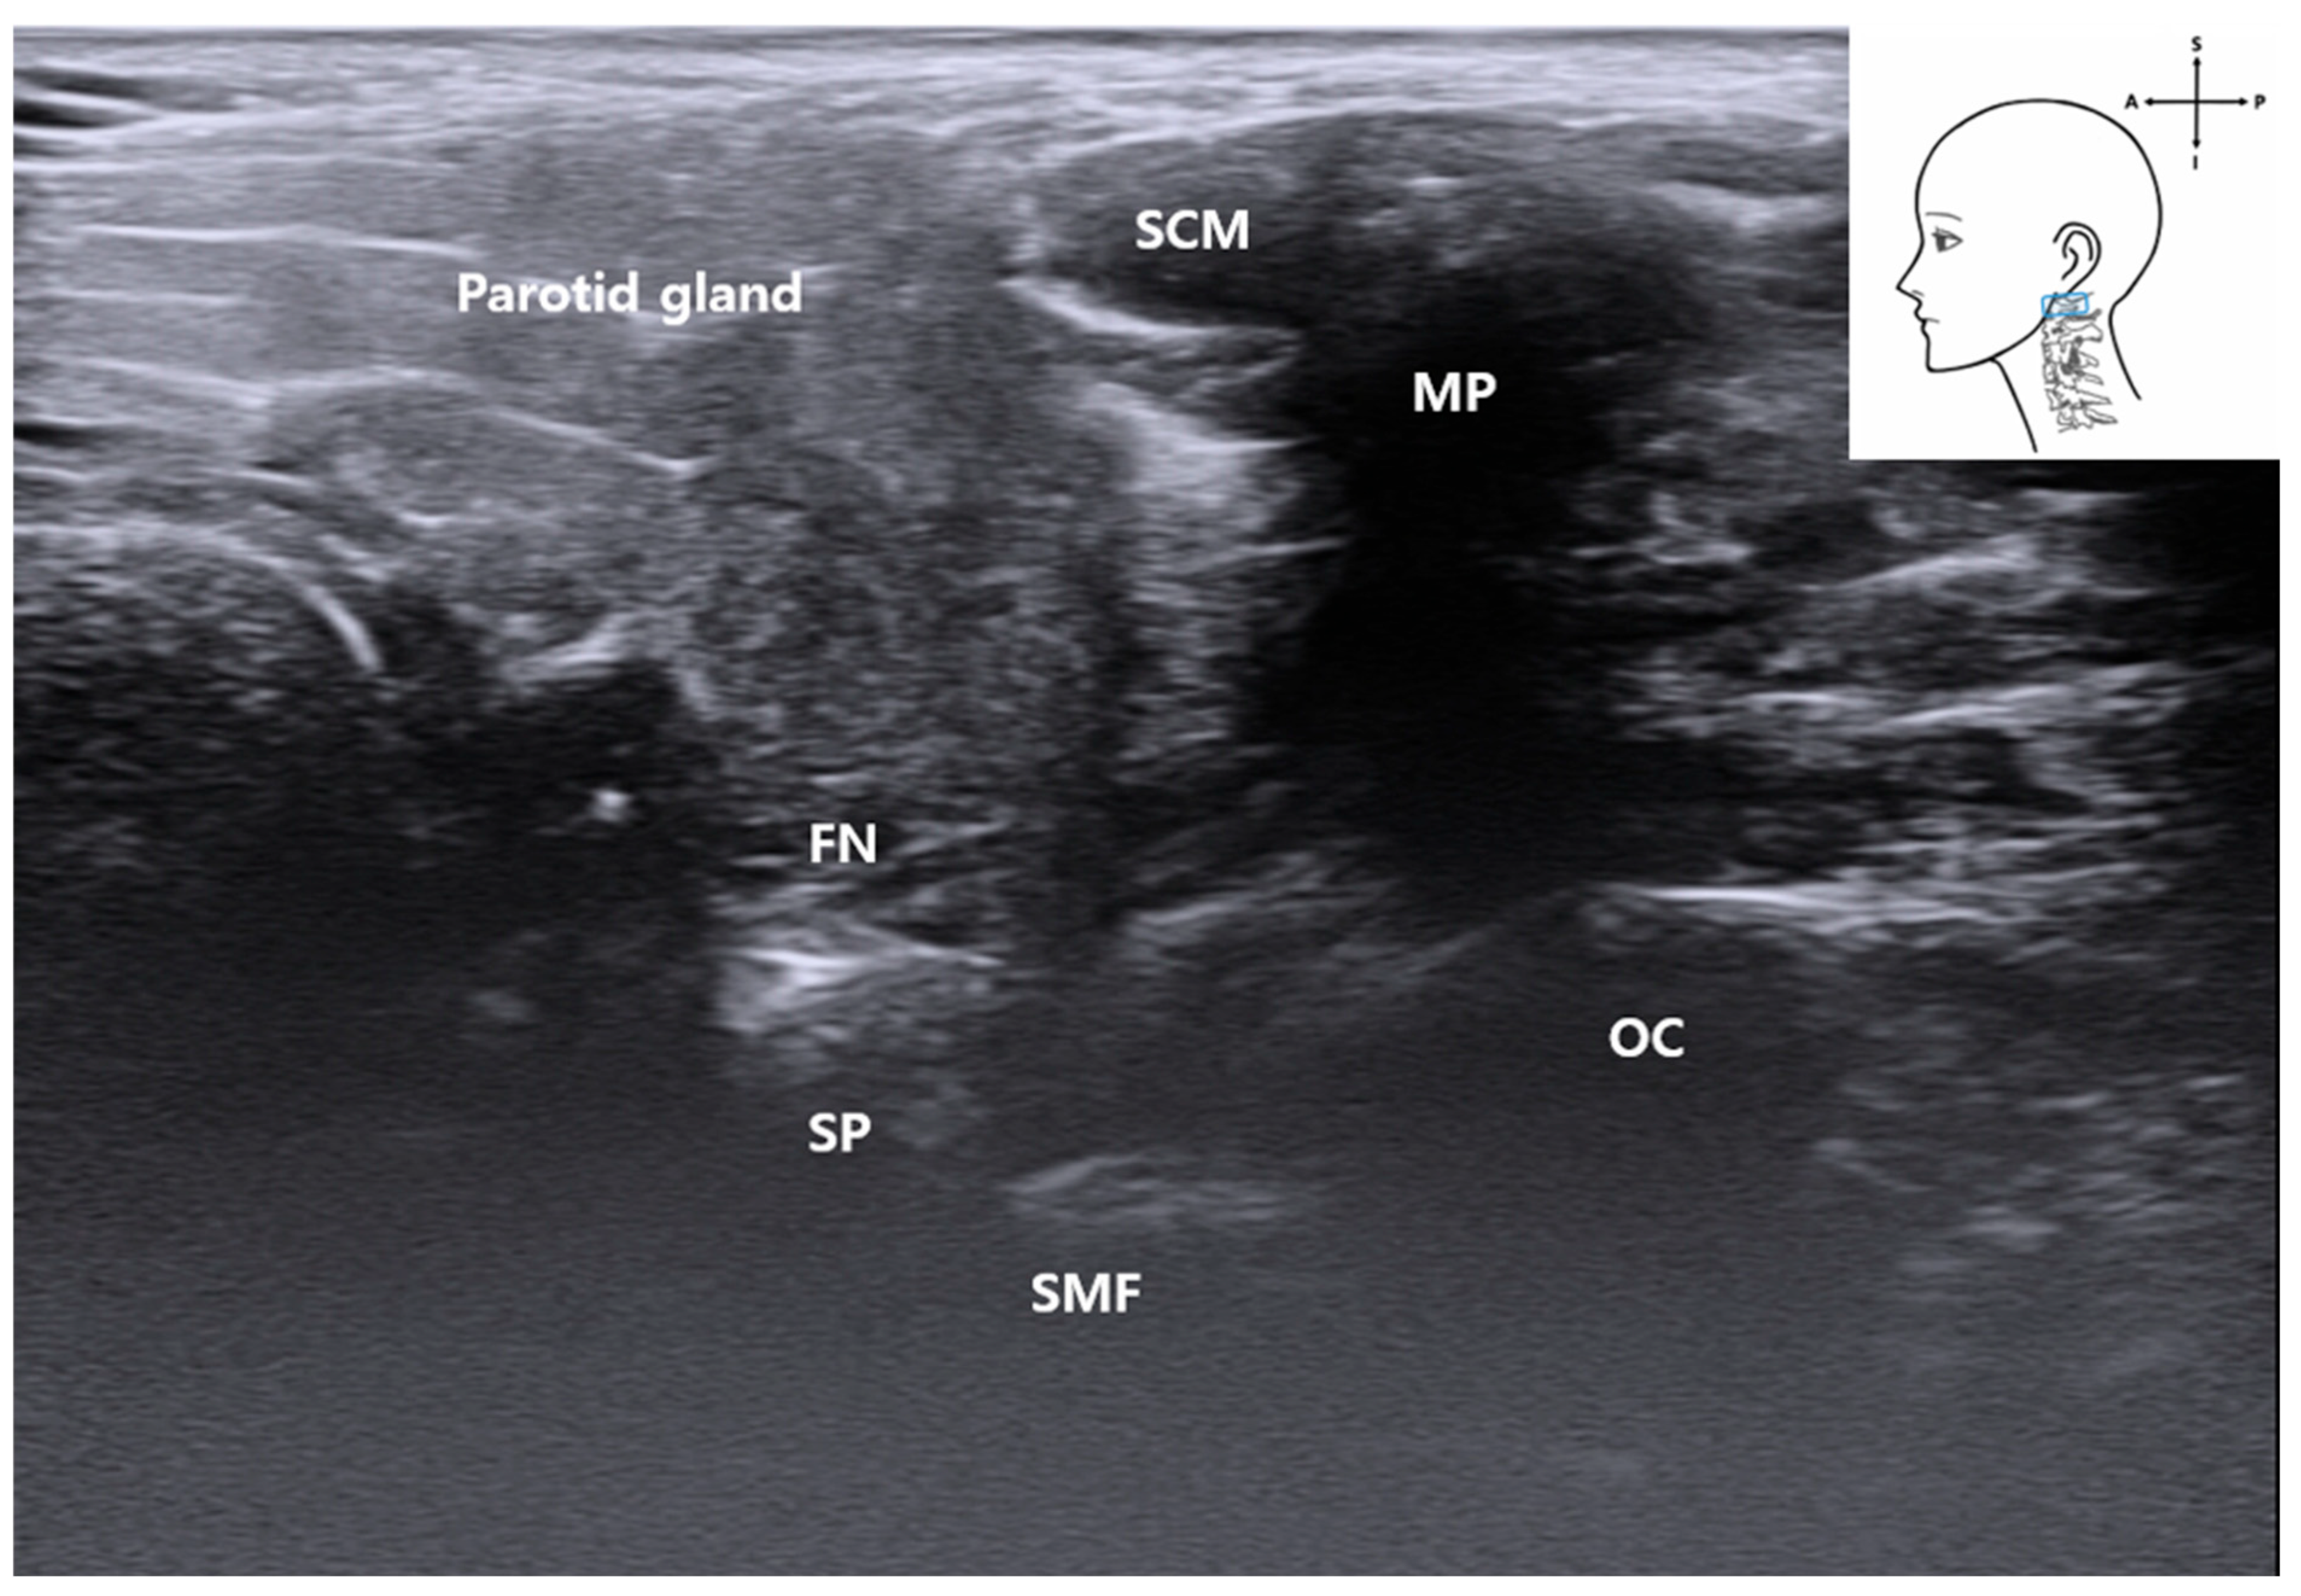

2. Materials and Methods

3.2. Probe Positioning

3.3. C1 Detection and Muscles

3.6. Visualization of the Stylomastoid Foramen and FN